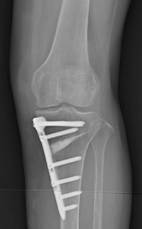

若年者から高齢者まで幅広く見られます。若年者ではスポーツによる外傷、高齢者では加齢による変形性変化を基盤に持つ場合が多く、各々治療法が異なります。若年者では半月を縫合するケースが多く、術後は2~3週の安静期間、その後はリハビリテーションが必要になります。半月の状態に応じて変わります。高齢者は半月が“経年変化”を生じていることが多く、損傷を受けた部分だけを切除する、部分切除で対応します。状態に応じて異なりますが、多くは1週間程度の入院です。